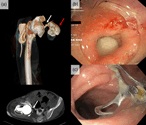

Over-the-scope clip (OTSC®) closure of a recto-acetabular fistula

Tobias S Schiergens and others

Journal of Surgical Case Reports, Volume 2018, Issue 4, April 2018, rjy074, https://doi.org/10.1093/jscr/rjy074